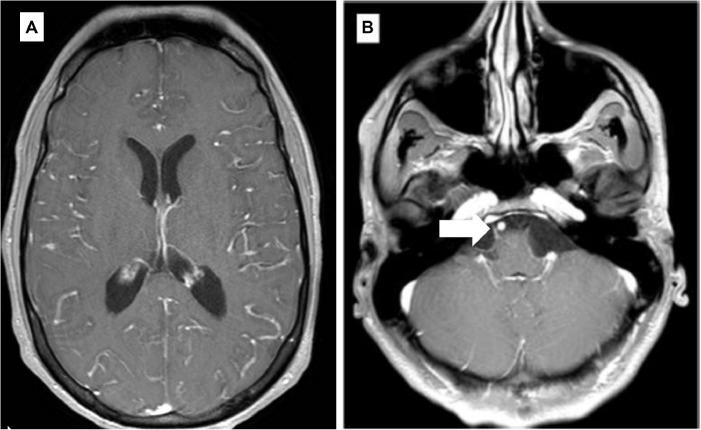

Central nervous system involvement in Hodgkin lymphoma is extremely rare, especially in nodular lymphocyte predominant Hodgkin lymphoma (NLPHL), which usually carries a favorable prognosis. Here we report a case of a young patient with NLPHL, who developed a progressive and fatal neurological deterioration requiring a very extensive work-up including two biopsies to obtain the diagnosis of T-cell/histiocyte-rich large B-cell lymphoma like transformation. This report, which includes post-mortem analysis, highlights the correlations between clinical, radiological, and biological data but also the difficulties encountered in reaching the correct diagnosis.

中枢神经系统受累于霍奇金淋巴瘤极为罕见,尤其是在结节性淋巴细胞为主型霍奇金淋巴瘤(NLPHL)中,该型通常预后良好。在此,我们报告一例年轻的NLPHL患者,其出现进行性且致命的神经功能恶化,需要进行非常全面的检查,包括两次活检,以确诊为T细胞/组织细胞丰富的大B细胞淋巴瘤样转化。本报告包括尸检分析,突出了临床、放射学和生物学数据之间的关联,同时也强调了在做出正确诊断过程中所遇到的困难。